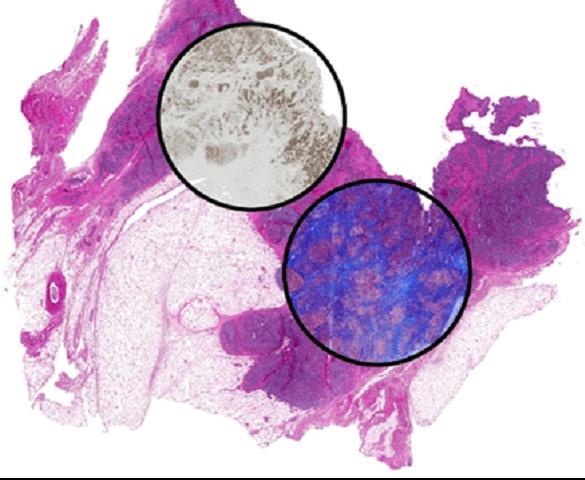

Histopathology is a cornerstone of modern biomedical research. Yet, the practice of histopathology has evolved just a few times -- non-specific stains in the late 19th century, immunohistochemical staining in the mid-to-late 20th century and digital imaging/computerized analysis at the turn of the 20th century. In all cases, prepared biopsy samples are stained and examined under a light microscope. This study reports a new approach to histology in which a team of engineers, pathologists and surgeon report the development of label-free chemical imaging to provide the same information as molecular stains. Led by Rohit Bhargava at the University of Illinois, the study is based on using infrared spectroscopic imaging for microscopy.

Instead of using stains, the spectra measure the chemical constitution of cells and tissues directly. By using computational techniques, the researchers were able to relate spectral properties to known staining patterns of tissue. The outcome is that that molecular stains can be reproduced without staining the tissue but by using the intrinsic molecular contrast of the tissue and computation. Thus, any sample can be stained for desired stains without material cost, time or effort while leaving precious tissue pristine for downstream analyses. Another use of the approach can be in the analysis of small amounts of samples, for example from a thin needle biopsy. In cases where materials are limited or there may be a need to closely correlate multiple expressed molecules, it may not be possible to obtain multiple samples from the same biopsy for multiple stains. The method developed in this study could be a solution, allowing the user to simply "dial-in" a required stain. The study is timely as it builds on the emergence of chemical imaging and maturation of computation from the sciences/engineering side and the drive to greater molecular content from the biomedical/clinical side. The development of this approach promises to have immediate and long term impact in changing pathology to a multiplexed molecular science -- in both research and clinical practice.